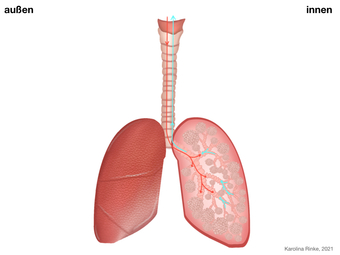

Lunge (Organ, Mensch)

Das Bild gehört zur Serie "Organe des Menschen". Das Bild verdeutlicht den Aufbau der menschlichen Lunge. Bild-Variante: Lunge mit Luftkreislauf; farbig; unbeschriftet. Es gelten die Nutzungsbedingungen der Mediothek und Pixiothek.

Lunge (Organ, Mensch)

(1024x768)